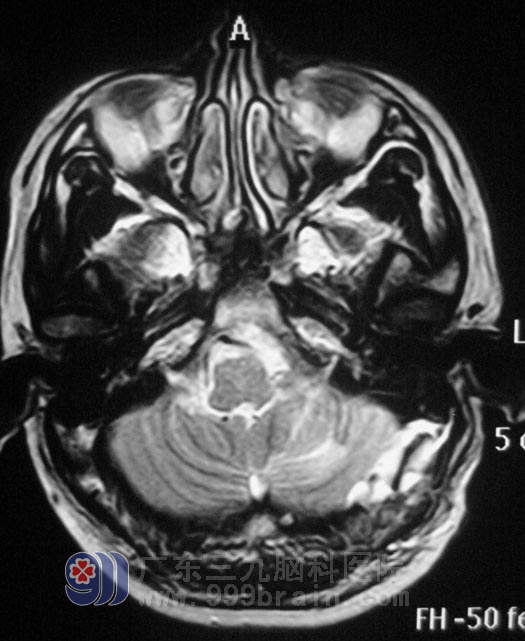

谢先生在一年前开始出现左耳听力变差,未行检查治疗,左侧听力进行性下降,伴间断性伴头痛,可忍受。头颅MRI结果提示:左侧桥小脑角区囊实性占位,考虑神经鞘瘤可能。

10月27日,广东三九脑科医院综合神经外科 鲁明主任主刀,在全麻下行左侧桥小脑角占位切除术+颅内压探头植入术,在显微镜下探查见桥小脑角鱼肉状肿瘤,包膜完整、血运丰富、质软、边界尚清,见肿瘤向前深入内听道,术中对三叉神经、后组颅神经等保护完好,手术顺利结束。术后病理结果为:(左侧桥小脑角区)神经鞘膜瘤。